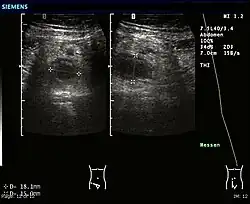

Ultrasound

Abdominal ultrasonography, preferably with doppler sonography, is useful to detect appendicitis, especially in children. Ultrasound can show the free fluid collection in the right iliac fossa, along with a visible appendix with increased blood flow when using color Doppler, and noncompressibility of the appendix, as it is essentially a walled-off abscess. Other secondary sonographic signs of acute appendicitis include the presence of echogenic mesenteric fat surrounding the appendix and the acoustic shadowing of an appendicolith.[59] In some cases (approximately 5%),[60] ultrasonography of the iliac fossa does not reveal any abnormalities despite the presence of appendicitis. This false-negative finding is especially true of early appendicitis before the appendix has become significantly distended. Also, false-negative findings are more common in adults where larger amounts of fat and bowel gas make visualizing the appendix technically difficult. Despite these limitations, sonographic imaging with experienced hands can often distinguish between appendicitis and other diseases with similar symptoms. Some of these conditions include inflammation of lymph nodes near the appendix or pain originating from other pelvic organs such as the ovaries or Fallopian tubes. Ultrasounds may be either done by the radiology department or by the emergency physician.[61]

-

Ultrasound showing appendicitis and an appendicolith.[62]

Ultrasound showing appendicitis and an appendicolith.[62] -

Ultrasound of a normal appendix for comparison. -

A normal appendix without and with compression. Absence of compressibility indicates appendicitis.[59]